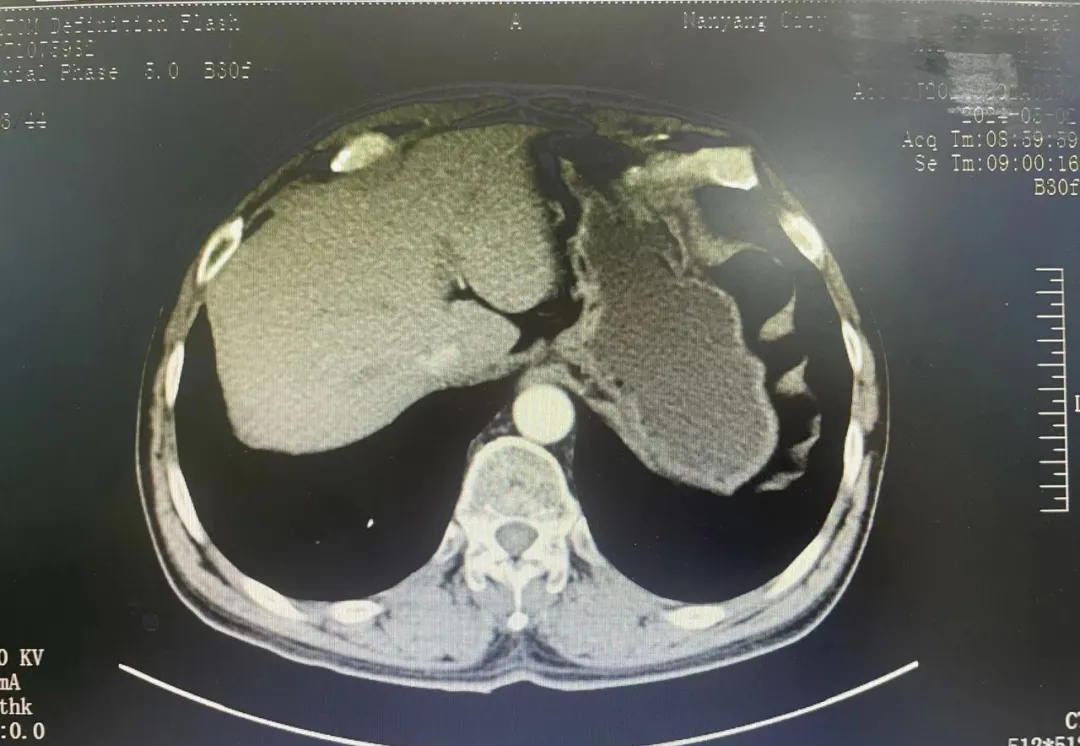

之后,我给患者做了胃镜检查,发现看不清楚,但能肯定不是肿瘤。那么,会是什么呢?我安排患者做增强CT扫描。结果提示一根肋骨顶在胃壁上,造成胃黏膜下隆起。

胃黏膜下隆起的原因找到了。可是,怎么会有一根肋骨顶在胃壁上?我详细询问患者,得知他以前是矿工,有过严重的外伤史,正是那次外伤形成的骨折愈合断端造成这个隆起,让他一直感觉不舒服。